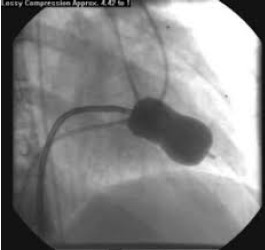

Paciente do sexo feminino, 38 anos, apresentava há seis meses classe funcional II. Foi submetida ao procedimento representado na figura abaixo. Na recuperação, apresentou-se taquicárdica, hipotensa e sudorética.

Com relação a esse caso, assinale a afirmação correta.